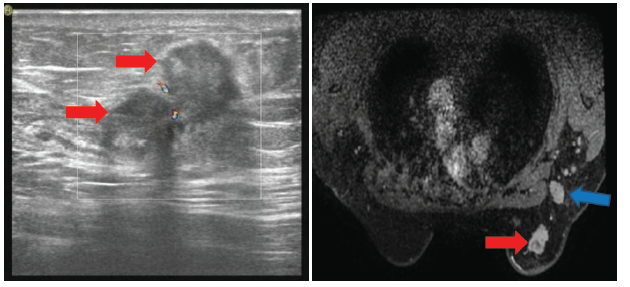

辅助检查:肿瘤指标正常。行乳腺彩超示:右乳10点钟位置距乳头5.0 cm可见一个大小为2.5 cm× 1.7 cm低回声光团, 形态不规则, 边界不清, 呈“ 蟹足样” 改变。右腋窝可见多个淋巴结回声, 边界清, 形态不规则, 皮髓质分界不清, 内回声不均匀, 其中一个淋巴结大小约2.5 cm× 1.9 cm。行乳腺核磁共振示:右乳外上象限乳腺癌伴右侧腋窝淋巴结转移, BI-RADS V类。见图1。行乳腺钼靶示:右乳外上象限恶性病变并右侧腋窝多发淋巴结转移, BI-RADS V类。见图2。行胸部-上腹部CT未见明显转移。